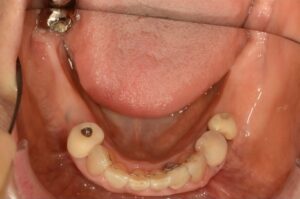

After

| 年齢・性別 | 82歳、女性 |

| 治療期間・回数 | 4ヶ月間、来院回数4回 |

| 治療方法 | 歯と歯の間に0.5mmのやすりがけをして歯の横幅を修正し、マルチブラケット装置(ワイヤー矯正器具)にて歯を配列 |

| 費用 | 検査料 55,000円 基本矯正料 220,000円 処置料 5,500円 / 月 |

| デメリット・注意点 | 唇に装置が当たって口内炎になる可能性 歯根吸収の可能性 調整のたびに2〜3日程度、上下の歯が接すると痛みが生じる |